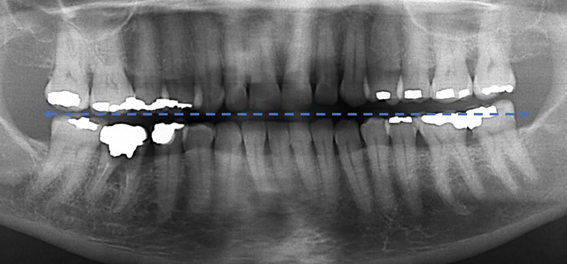

Radiographic images compatible with excess or lack of restorative material was the most common iatrogenesis in the analyzed images (61.57%), followed by insufficient endodontic treatment (26.27%) where findings of lack of obturator material, apical obturation below were found beyond the radiographic apex. Also, 74 (12.16%) radiographs showed two or more types of iatrogenesis Figure 1 & 2.

Figure 6 Panoramic radiographic technique performed with the Frankfurt Plan slightly higher than the standard position, to "open" the interproximal spaces in the posterior teeth, making the smile line straighter .